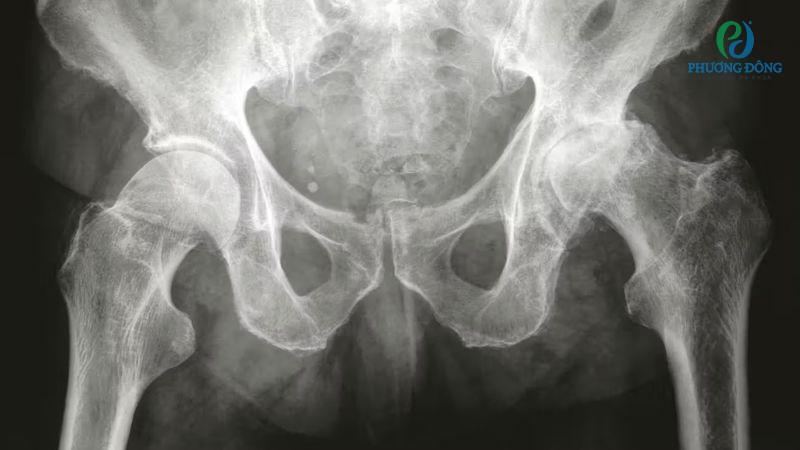

Khớp háng

Khớp háng có bao hoạt dịch lớn nhất nằm ở mấu chuyển lớn, giữa cơ mông và mấu chuyển. Với vị trí này, bao khớp hỗ trợ giảm ma sát khi cơ thể chạy nhảy, xoay hông hoặc đi bộ, đảm bảo khả năng vận động linh hoạt và dễ dàng.

Bao khớp háng lớn nhất nằm ở giữa cơ mông và mấu chuyển

- Chụp X-quang khớp xem xét cấu trúc khớp bị đau có bị biến dạng, xuất hiện khối u hay dị vật bất thường không.